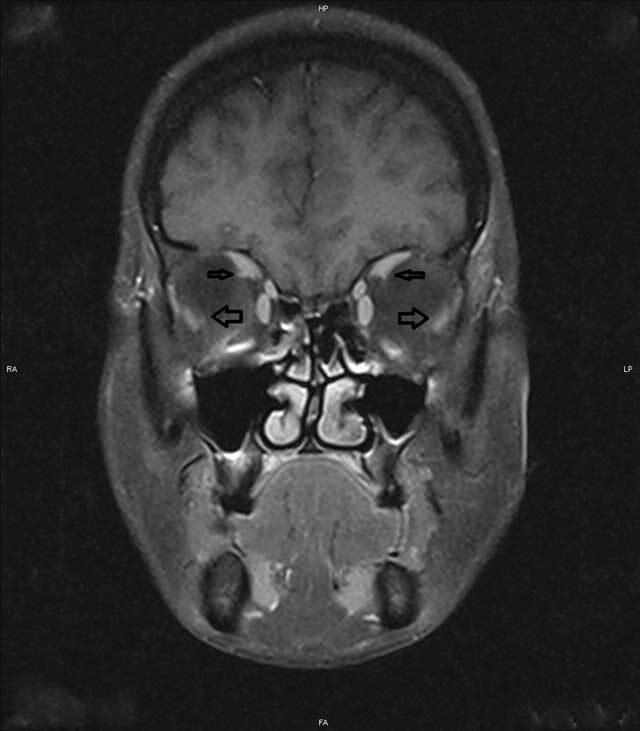

Methods: A 47-year-old lady with high myopia, high axial length, progressive esotropia, slippage of the lateral rectus (LR) inferiorly and superior rectus (SR) medially on magnetic resonance imaging (MRI) was diagnosed with heavy eye syndrome. Unaugmented loop myopexy without medial rectus (MR) recession was offered.